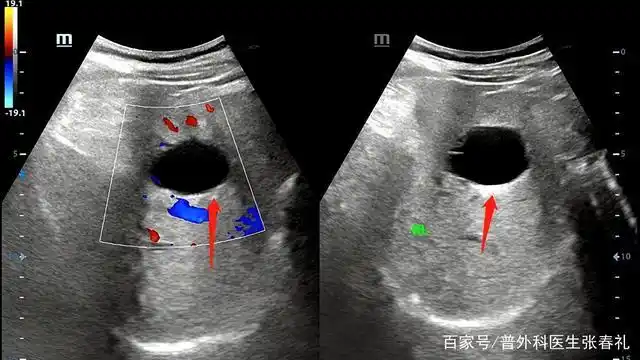

3月13日腹部b超结果:肝囊肿(11×8mm),腹部胀气.

肝囊肿超声诊断